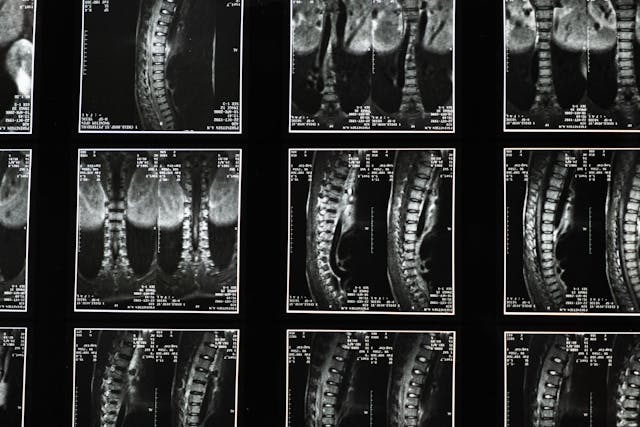

Neoperativno lečenje diskus hernije

Diskus hernija je jedan od najčešćih uzroka bola u donjem delu leđa i širenja bola niz nogu. Nastaje kada dođe do pomeranja ili oštećenja diska između pršljenova, što može izazvati pritisak na nerve.

U Poliklinici Savić u Nišu diskus hernija se leči primenom savremenih metoda fizikalne terapije i terapije bola, sa ciljem smanjenja simptoma i vraćanja normalnom funkcionisanju bez operacije.